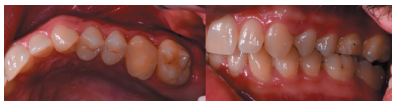

After 2 months, a new clinical review (Figure 17) and a radiograph was performed by a periapical radiograph (Figure 18), proceeding to remove the ferulization. After 3 months, another clinical review (Figure 19)

and a radiograph was performed by parallel periapical radiograph (Figure 20), where an adequate bone formation can be observed around the transplanted tooth.

In addition, a good clinical and radiographic result was obtained, after 5 months of follow-up, describing the patient a good masticatory function and the absence of adverse effects, which are described in the literature with a rate of 4%, highlighting among them the ankylosis and root resorption.